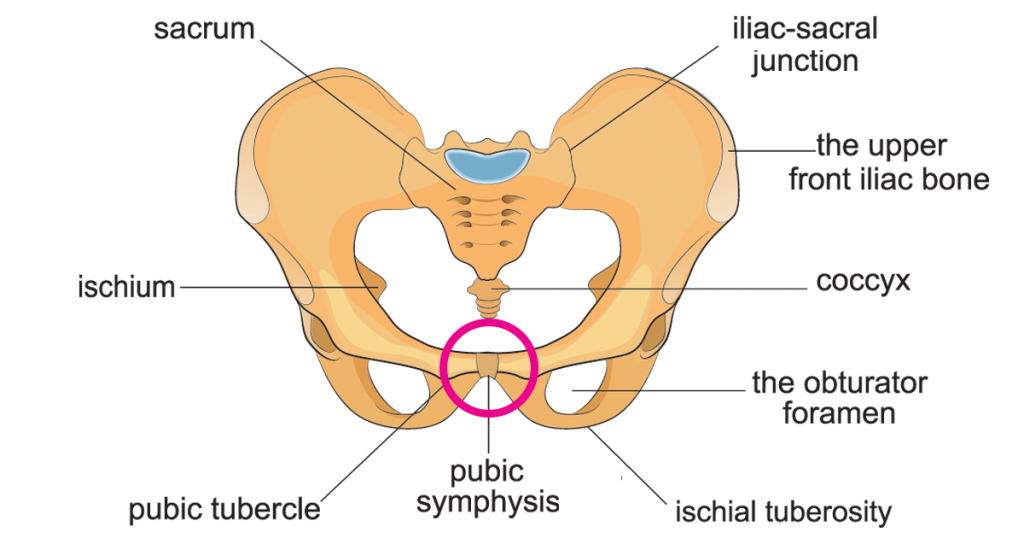

- Key Landmarks:

- Pubic crest

- Pubic tubercle

- Inguinal ligament

- Pubic symphysis